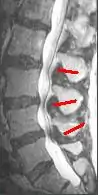

MRI of the lumbar spine showing spinal stenosis

Since an MRI provides excellent imaging of blood vessels and tissues, it is recognized as the best type of imaging to observe signs associated with lumbar compression. The precise measurement of the diameter of the spinal canal is a particularly important component when determining the severity of the stenosis itself.[2] High strength 3-Tesla MRI machines are being utilized due to the increased vascular imaging capabilities. Better resolution capacity allows for more detailed observations by the healthcare provider. The sharp contrast of the high power MRI outlines details in the vertebra that are critical when examining a patient with lumbar spinal stenosis who may need a laminotomy.[1] MRI scanning post invasive surgery is used to see the quality of the surgery itself, yet the appropriate postoperative time elapsed before conducting an MRI is a debated topic.[2]